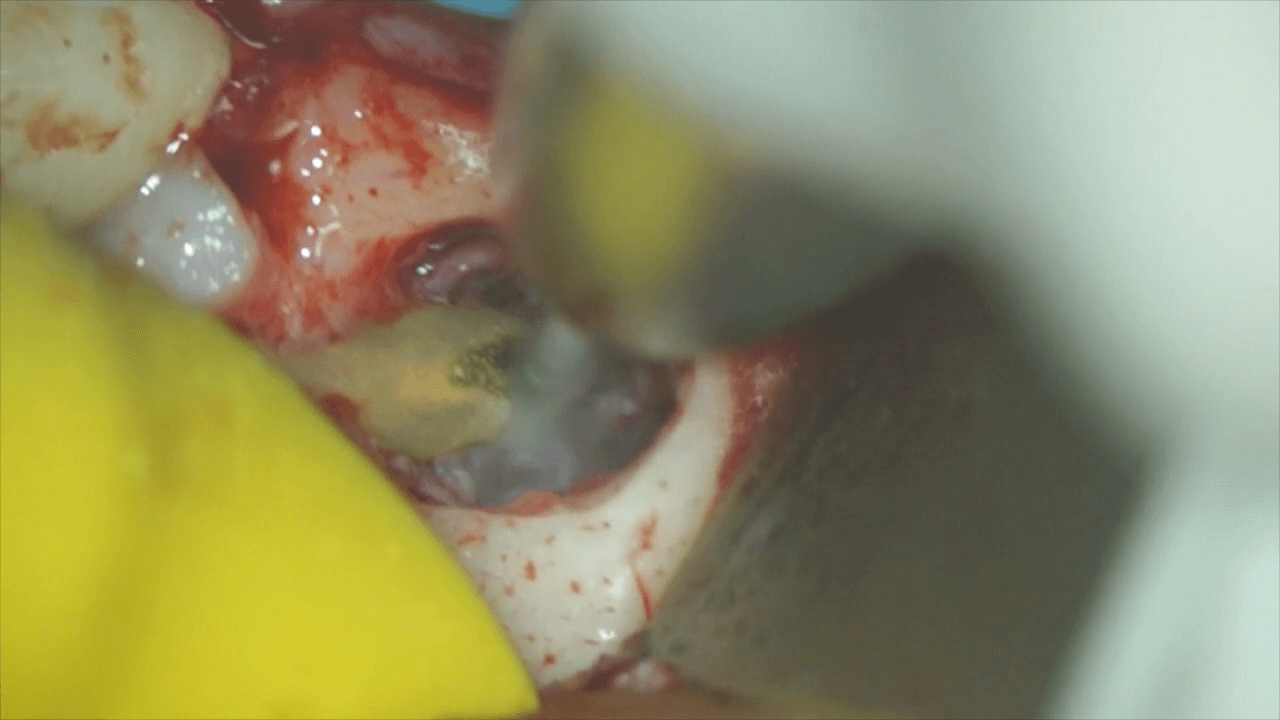

マイクロスコープを用いて、処置を行います。まずは、根の先をカットします。と、同時に歯石も取り除きます。

そして、その他に汚れの取り残しがないか、確認します。

実際の処置の動画を提示致しますので、ご覧ください。